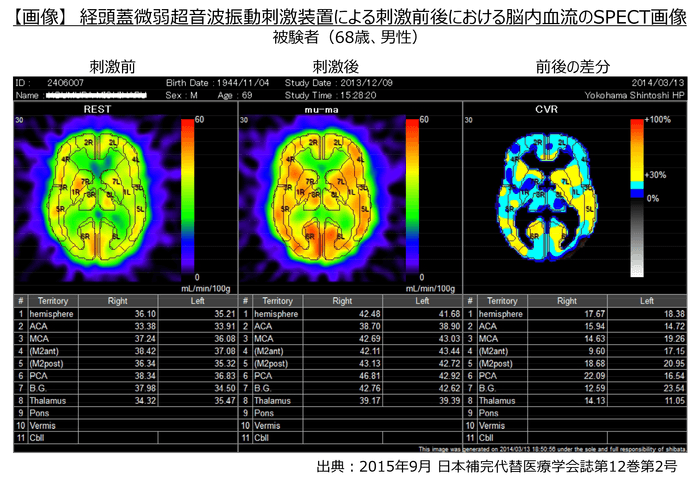

・その結果、イルカが発する30kHzの周波数帯で微弱な振動(2ミリワット/cm2以下)を初老期の健常人に20分間照射することにより脳血流が約15%増加したことが確認されました。

・故小阪憲司先生(世界で初めて脳内・異常蛋白質が原因となるレビー小体型認知症を報告、横浜市立大学名誉教授・精神科医)のご指導のもと、神奈川歯科大学附属病院 認知症・高齢者総合内科 眞鍋雄太教授とともに、中等度のDLB患者に対して特定臨床研究を実施した結果、特に運動機能障害の顕著な改善が認められました。(下記画像参照)